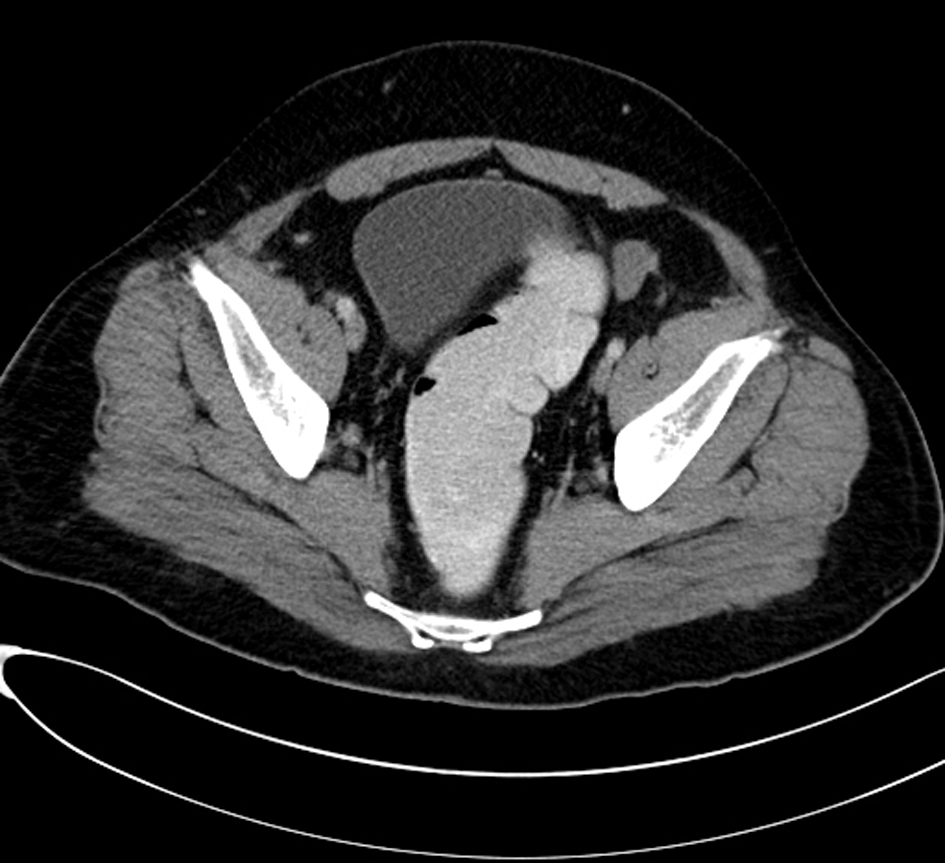

Computed tomography (CT) scan examination of the abdomen and pelvis was performed after administration of intravenous (IV) contrast material in portal venous phase which shows an empty scrotal sac with absence of the testicles and spermatic cord bilaterally (Fig. 1). A large homogenous mass is identified within the retro peritoneum of the right lower abdominal quadrant associated with small central area of low attenuation could represent an areas of cystic necrosis. No associated calcification is seen (Fig. 2). Small oval and homogenous structure is seen within the left aspect of the hemi pelvis just adjacent to the inguinal ring which represents a small atrophied left testicle with no masses (Fig. 3). There are multiple homogenous and matted lymph nodes metastasis located within the right Para-aortic region in close relation to the right renal hilum (Fig. 4).

![]() Click for large image | Figure 3. Small oval and homogenous structure is seen within the left aspect of the hemi pelvis just adjacent to the inguinal ring which represents a small atrophied left testicle with no masses. |